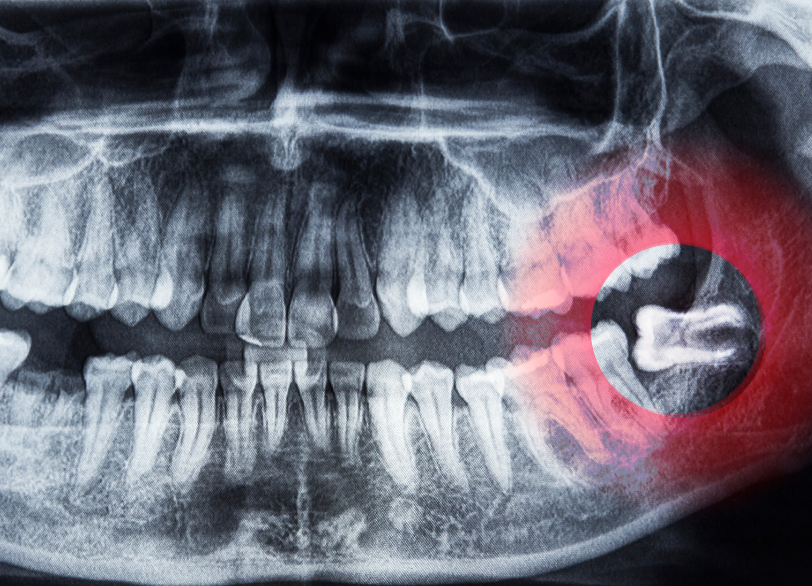

親知らずは、一番奥に後から生えてくる永久歯です。

現代人は顎が小さくなってきているため、親知らずがまっすぐ生えるためのスペースがなく、横向きに生えたり、骨の中に埋まったままになったりすることが少なくありません。

特に、親知らずの抜歯やインプラント手術などでは、顎の骨の中を走る太い神経や血管の位置を、三次元的に、そしてミリ単位で正確に把握しておくことが、偶発的な事故を防ぐ上で極めて重要になります。

当院では、歯科用CTを導入し、従来の平面的なレントゲンでは決して分からなかった骨の形態や厚み、神経・血管との位置関係を、事前に詳細に確認します。

このCTによる「見える化」が、安全な手術計画の立案を可能にするのです。